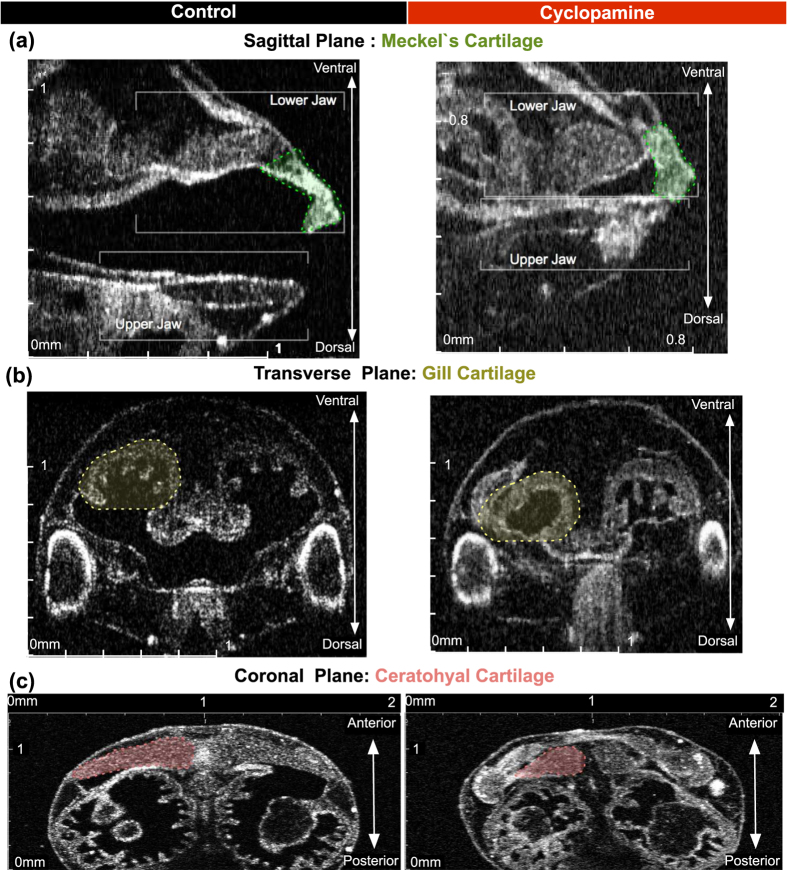

Figure 4. Qualitative neural crest defects in Xenopus with cyclopamine treatment.Stage 46 uninjected control tadpole compared to cyclopamine treated tadpoles and demonstrated the teratogenic effects. (aâc) Left column shows the control and the right column shows the cyclopamine treated tadpole. In cyclopamine treated tadpoles both jaws were short and thick. Meckel and ceratohyalcartilage were smaller and gill cartilages were nearly lost. (Scale Bar on x and y axis: 0â2âmm).

Figure 5. Quantitative neural crest defects in Xenopus with cyclopamine treatment.(a/aâ²âc/câ²) Stage 46 control tadpole compared to cyclopamine (2.5âmg) treated tadpoles. The tadpole is positioned on the ventral side up, and the OCT imaging plane scrolled along the z-axis until the largest mid-lateral portion of the cartilages is visualized. We acquired a set of 3D data. On these coronal sections a line between two points traveling along the mid-corpus of the Meckelâs and ceratohyalcartilage is measured. Then the largest middle and lateral borders along the corpus of the most anteriorgill are marked, and the midline length is measured. Quantitative analysis demonstrated reduction in length and area in treated tadpoles on the coronal plane. L: left, (Mann-Whitney test; pâ<â0.05) (*pâ<â0.05/**pâ<â0.01/****pâ<â0.0001) (Bars represent mean with 95% confidence interval).